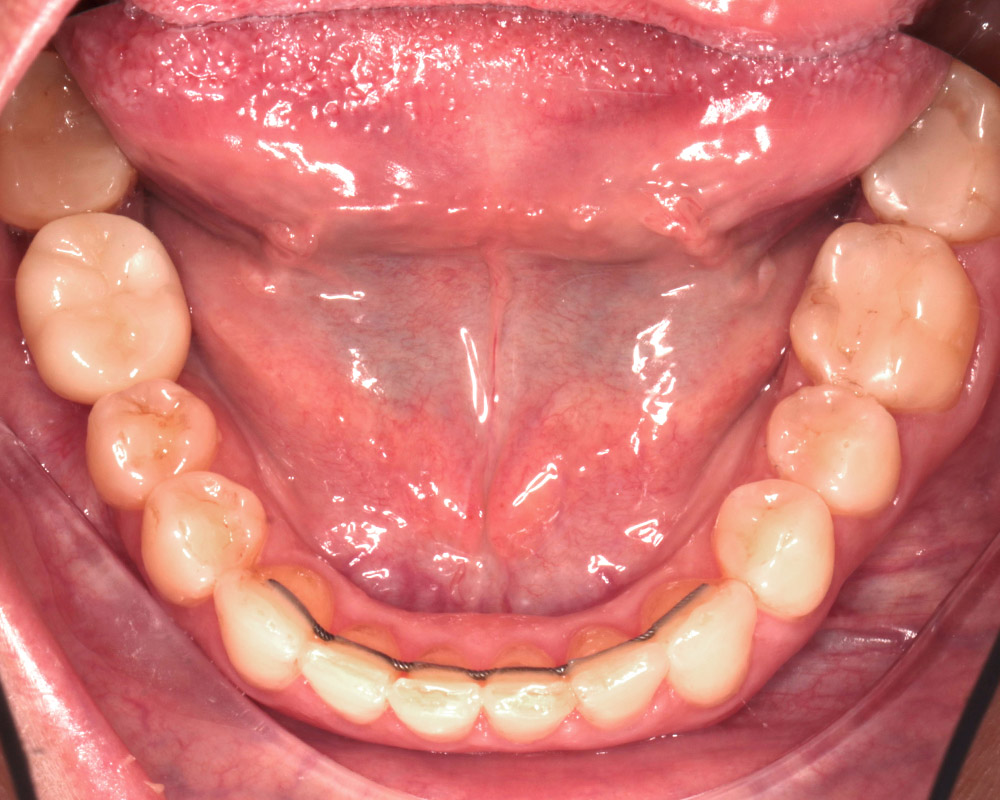

Кейс 21

Количество кап ВЧ 32

Количество кап НЧ 32

ДО

ПОСЛЕ